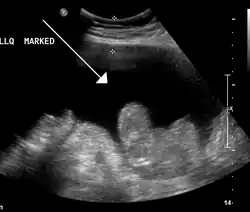

Imagem de ultrassom que mostra ascite em uma pessoa com câncer de abdômem

A Ecografia é usualmente utilizada na investigação do quadro previamente a medidas para remover o fluido da cavidade abdominal. Esta pode revelar as dimensões e forma dos órgãos intra-abdominais e estudos Doppler mostram a direcção do fluxo na veia Porta bem como detectar a Síndrome de Budd-Chiari ou a trombose da veia porta. Adicionalmente, o ecografista pode ectuar uma estimativa da quantidade de líquido ascítico e ascites de difícil drenagem podem-no ser sob controlo ecográfico. A Tomografia computadorizada Abdominal é um método mais sensível para revelar a estrutura e morfologia dos órgãos abdominais.